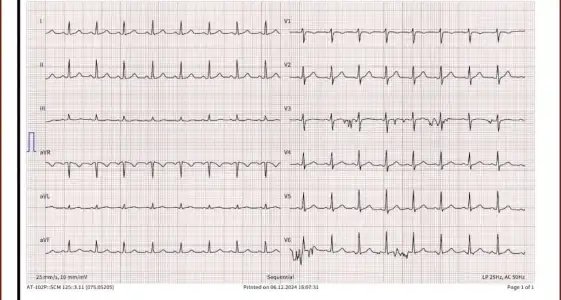

Merhaba bugün kadın hastalıkları ve doğum bölümüne gittim rahim ağzında yara var diye ve bana yakma önerdiler bi kaç test yaptılar anestezi için ve sonuçları pazartesi göstericem ama sonuçlar çıktığı için merak ediyorum aranızda anlayan veya doktor olan biri varsa cevaplayabilirmi rica etsem?

IMG_8035.webp32,3 KB · Görüntüleme: 115

IMG_8036.webp32,2 KB · Görüntüleme: 112

IMG_8037.webp20,9 KB · Görüntüleme: 115

IMG_8038.webp21,8 KB · Görüntüleme: 104

IMG_8039.webp21,3 KB · Görüntüleme: 108

IMG_8040.webp18 KB · Görüntüleme: 105

IMG_8041.webp20,9 KB · Görüntüleme: 101

IMG_8042.webp40,6 KB · Görüntüleme: 115